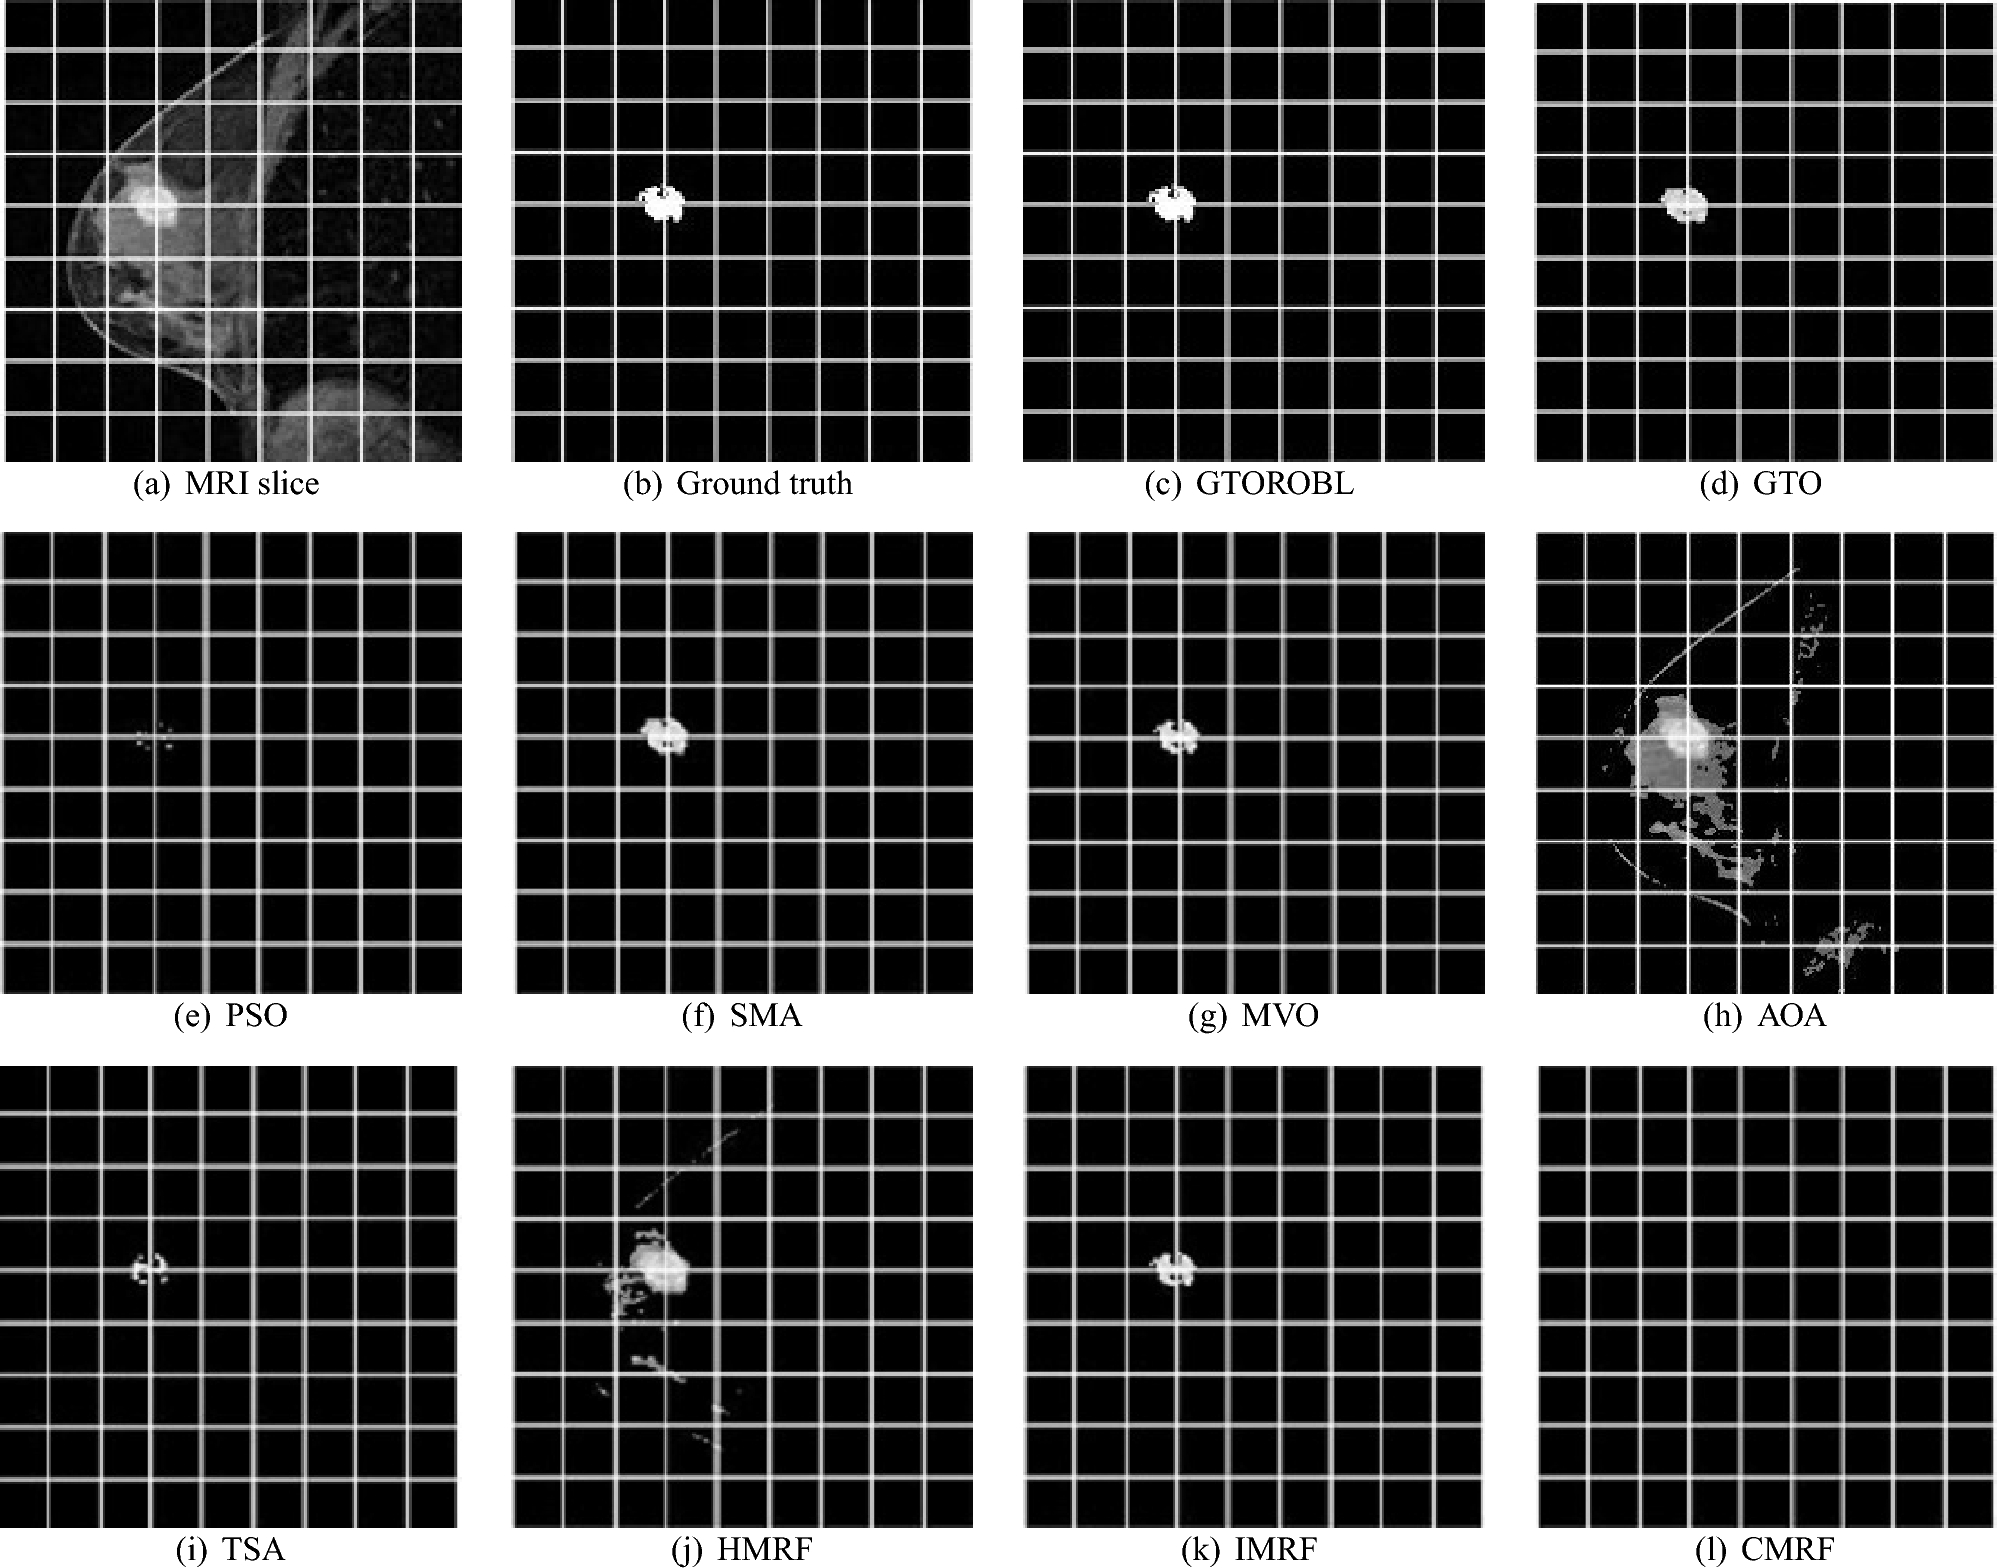

For patient-1 (a) MRI slice, (b) ground truth, and (c–l) GTORBL, GTO, PSO, SMA, MVO, AOA, TSA, HMRF, IMRF, and CMRF respectively.